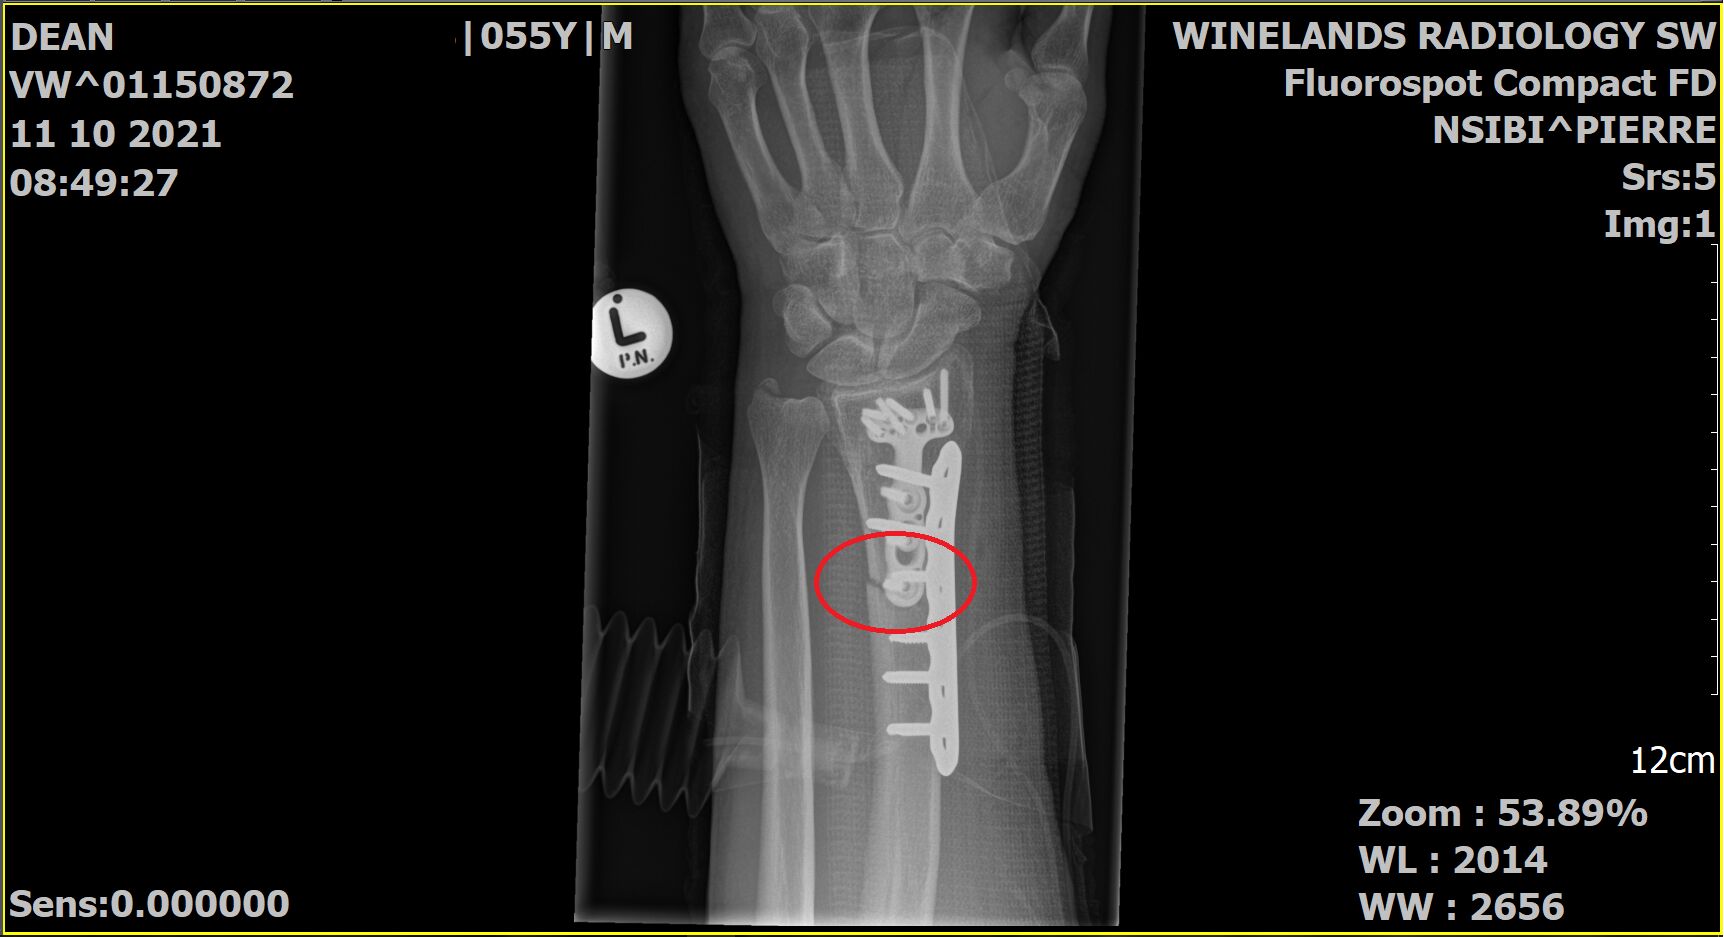

Surgery went well. It turns out it was a clean break at the base of the existing plate, so healing time should be short. The Surgeon intended to remove the original plate and replace it with a single longer one, but couldn’t get the locking screws to undo so just overlapped the new plate with the old one.